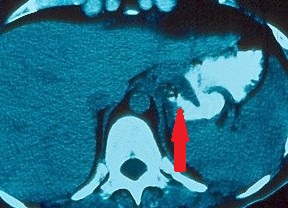

Contrast-enhanced CT of the abdomen, revealed a grossly distended stomach with mild diffuse thickening of its wall (red arrow)